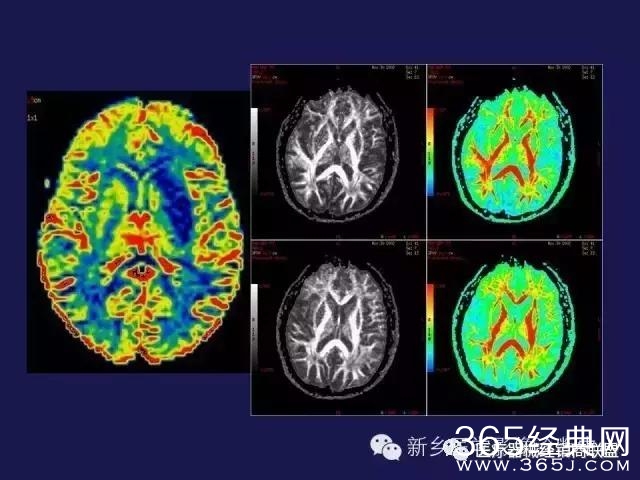

CT、MRI很难?NO,今日我们一起来学习一下如何读CT、MRI!

内行看门道:

整整90张图